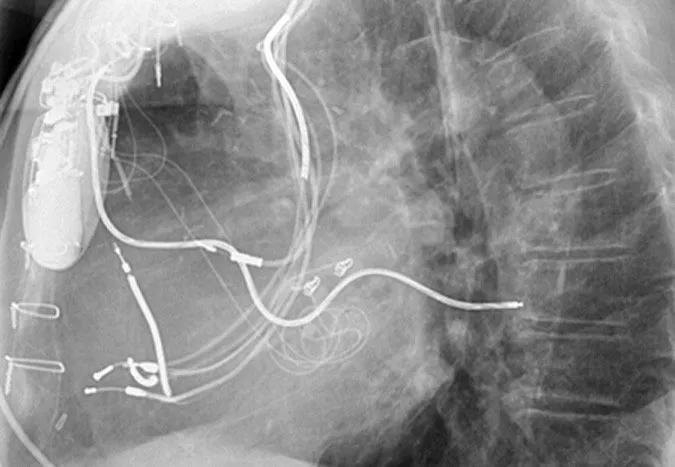

Various types of CIEDs are used to restore a normal rhythm when a heart starts beating too slowly, too fast or irregularly. They range in sophistication from a simple, single-chamber pacemaker with one lead to a biventricular pacemaker with defibrillator, which has three leads. Regardless of the number of leads, all CIEDs have a battery that sends electrical impulses down the wires into the heart muscle to make itcontract.